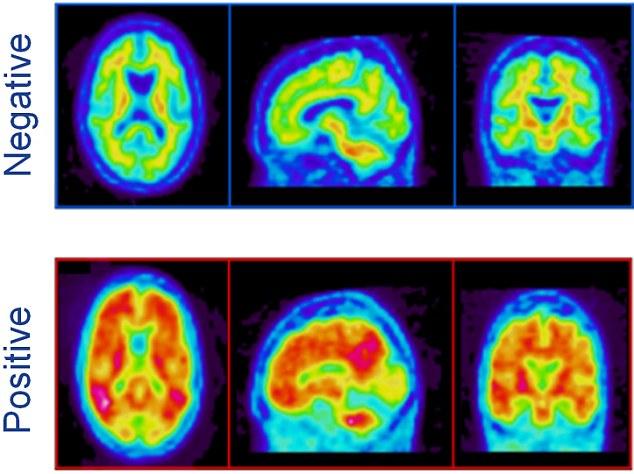

Εγκέφαλος αρνητικός (πάνω) ή θετικός (κάτω) στην άνοια